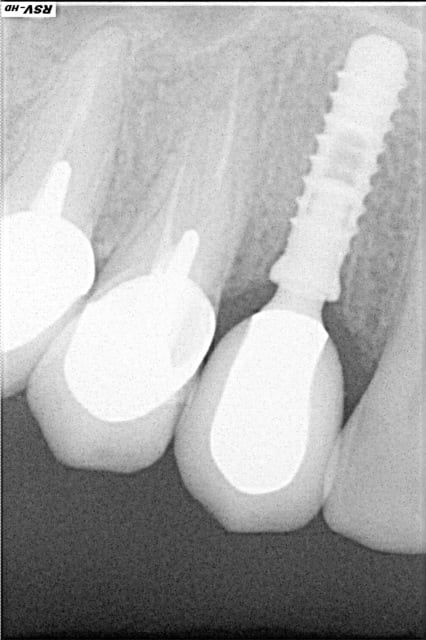

rx à j=0 et j+4 mois

ce qui est surprenant , c'est la présence d'os au niveau du col.

Oui on connait chez Leone mais reproductible sur toute la gamme. C'est qu"est que je dit! Mais nous c'est démontable et indexé. Un vieux cas en rx 5 ans entre les deux rx.